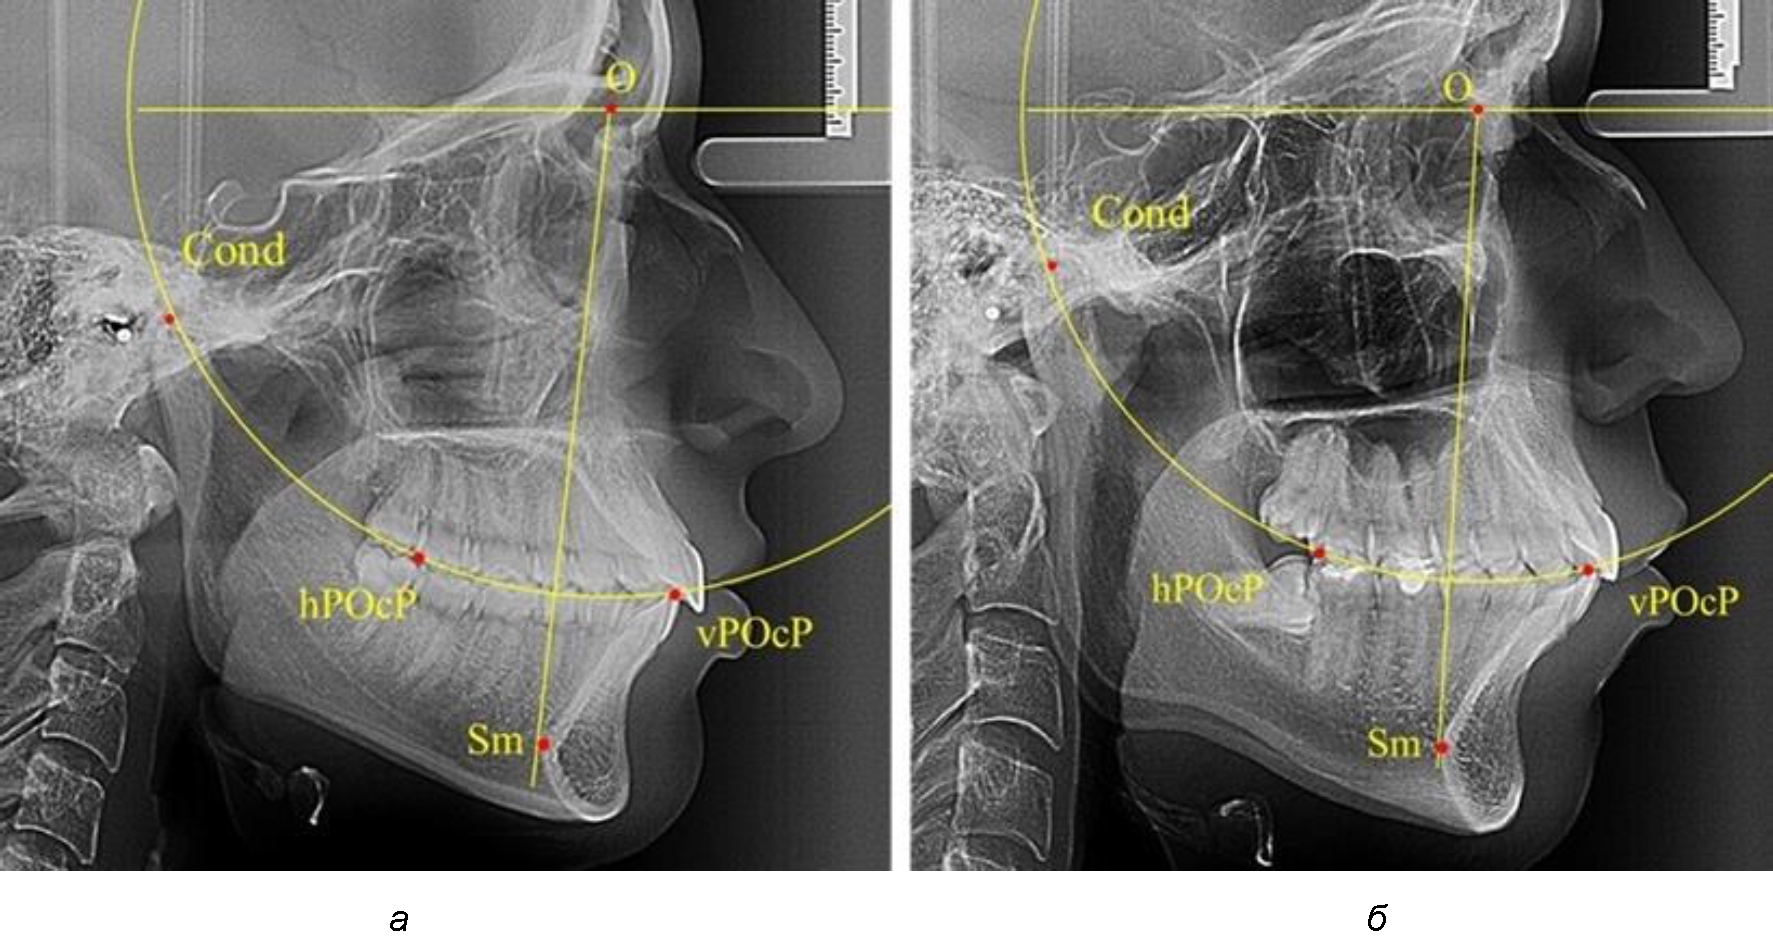

В группе рентгенограмм с ретрузионным положением резцов также проводилось распределение на подгруппы с учетом широтных размеров подбородочного выступа.

Анализ результатов показал, что практически при всех вариантах подбородочного выступа в данной группе исследования первые премоляры, как правило, располагались либо на стресс-оси Bimler, либо позади. Рентгенограммы пациентов с ретрузионным положением резцов при широком и среднем варианте подбородочного выступа представлены на рис. 4.

Таким образом, для людей с ретрузионным типом зубочелюстных дуг характерно расположение первых премоляров позади стресс-оси либо на средней линии, и этот показатель не может быть использован в качестве выбора метода лечения аномалий для данной группы исследования вне зависимости от формы подбородочного выступа.

Рис. 4. Положение первых верхних премоляров при ретрузии с широкими (а) и средними (б) размерами подбородка